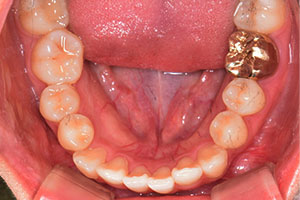

치료증례 전후사진

Before & After